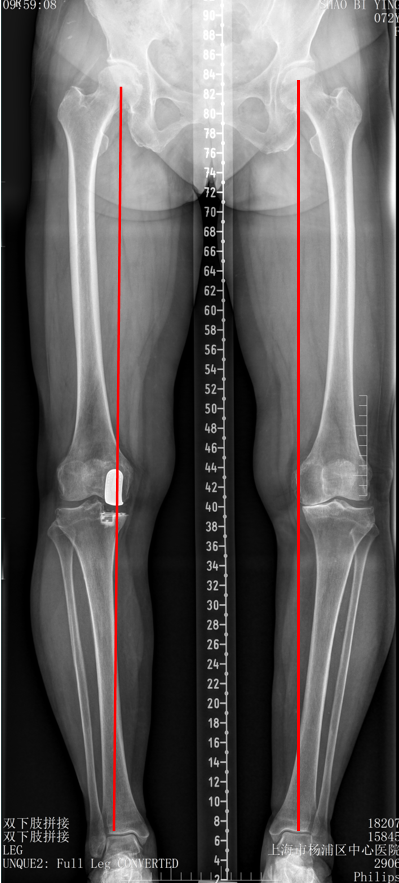

五、一期双单髁置换LINK:registered: SLED假体位置

双间室OA行Bi-UKA

正位片标准胫骨和股骨假体位置

AP位假体位置:内侧和外侧单髁分别按照各自的手术原则独立开展,假体的位置也按照各自的标准进行考量,需要综合考量的是胫股角,关节线,中央髁间隆突。